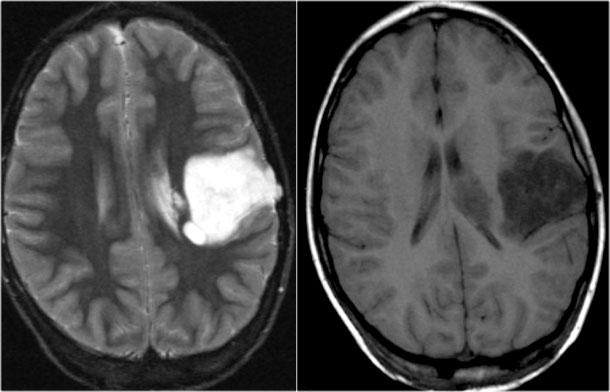

FLAIR axial, DWI axial và T2W coronal cho thấy hải mã tăng tín hiệu với sừng thái dương của não thất bên bị thu hẹp nhẹ, phù hợp với phù nề hải mã.

DWI cho thấy hạn chế khuếch tán do phù nề độc tế bào trong giai đoạn cấp tính của trạng thái động kinh liên tục.

T2W axial cho thấy hải mã tăng tín hiệu nhưng phì đại với hình ảnh dạng bong bóng.

Đây là hình ảnh điển hình của DNET hay u thần kinh biểu mô loạn sản phôi thai, sẽ được thảo luận chi tiết ở phần tiếp theo.

T1W coronal sau tiêm thuốc tương phản từ cho thấy hải mã phì đại không ngấm thuốc tương phản từ.